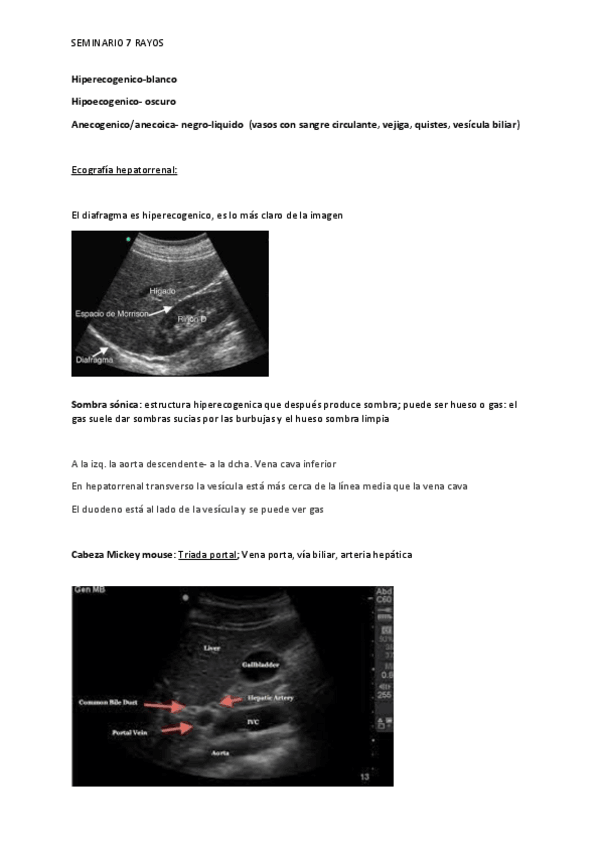

He publicado nuevos practicas de 4º Radiología y Medicina Física: SEMINARIO-7-ECOGRAFIA-RADIOLOGICA.pdf

5 páginas